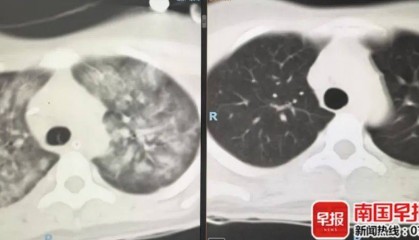

贵港一女子误服农药抢救多日未好转,家属刷手机看新闻迎转机

南国早报全媒体记者 玉浩 报料邮箱:news@ngzb.com.cn 4月30日,贵港一误服农药敌草...